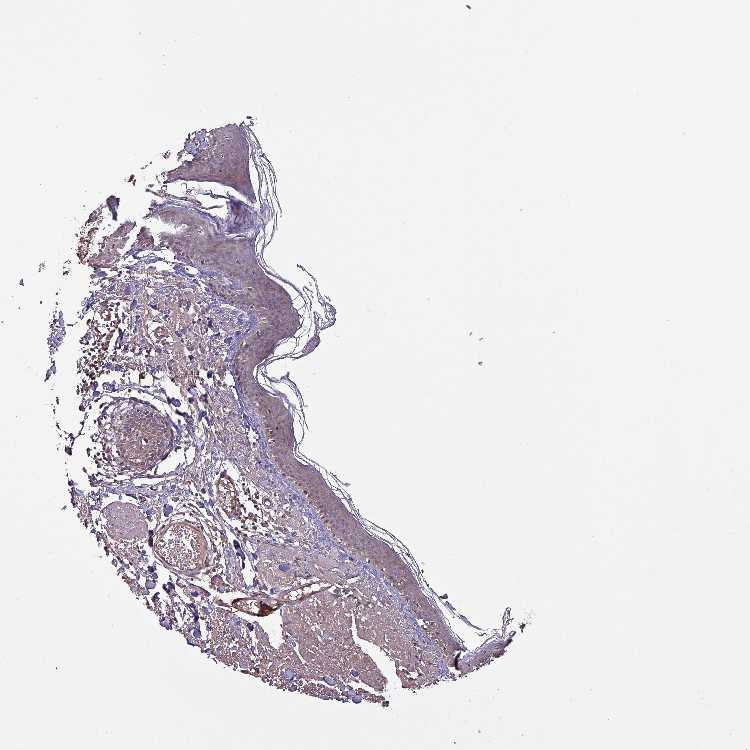

SKIN 2 - Antibody stainingi

Antibody staining in the annotated cell types in the current human tissue is reported as not detected, low, medium, or high, based on conventional immunohistochemistry profiling in selected tissues. This score is based on the combination of the staining intensity and fraction of stained cells.

Each image is clickable and will lead to virtual microscopy that enables deeper exploration of all samples and also displays staining intensity scores, fraction scores and subcellular localization as well as patient and tissue information for each sample.

Antibody HPA051836

Epidermal cells Medium